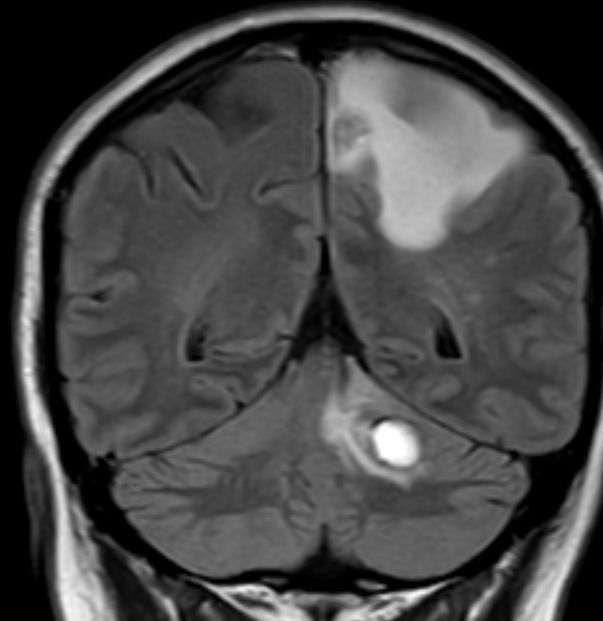

| Hirnmetastasen: Fallbeispiel frühe Hirnmetastasen nach regionalem Rezidiv | 68-jähriger Mann, der vor 4 Monaten ein Melanom des linken Unterschenkels pT1a pN2b M0 mit Metastasen in der linken Leiste hatte. Histologie: Naevus-assoziierte superfiziell, spreizendes Melanom. Nach OP und Defektverschluss verzögerte sich die Strahlentherapie durch ein ausgedehntes Serom. Während der Bestrahlung traten eine Kraftminderung, gesteigerte Reflexe und Sensibilitätsstörungen im rechten Bein auf. Das MRT zeigt 2 Hirnmetastasen. | |||